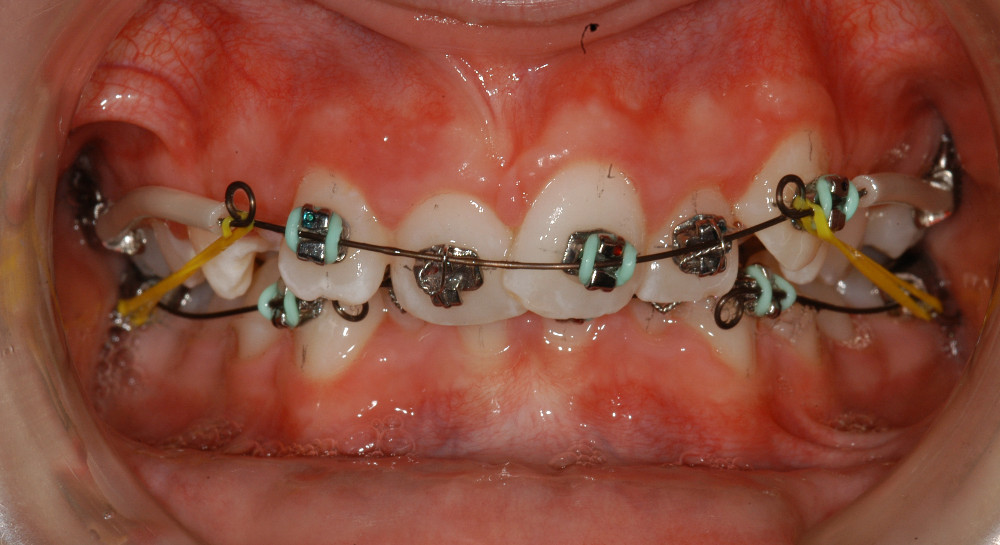

Das Wichtigste zuerst: Unsere fixe «Plättlispange» funktioniert anders als die meisten anderen fixen Spangen. «TIP-EDGE Plus Orthodontics» ist duch fogenden Eigenschaften gekenntzeichnet:

- ‚Tip-Edge‘ kippt die Zähne anfänglich mit ganz leichten Kräften an ihre richtige Position im Zahnbogen, denn Zähne wollen sich naturgemäs durch Kippen bewegen

- Dazu hängt der Patient nur zwei ganz leichte Elastiks ein – sonst nichts

- Ein optimales und stabiles Behandlungsresultat basierend auf sehr langer Erfahrung mit dieser Therapieform.